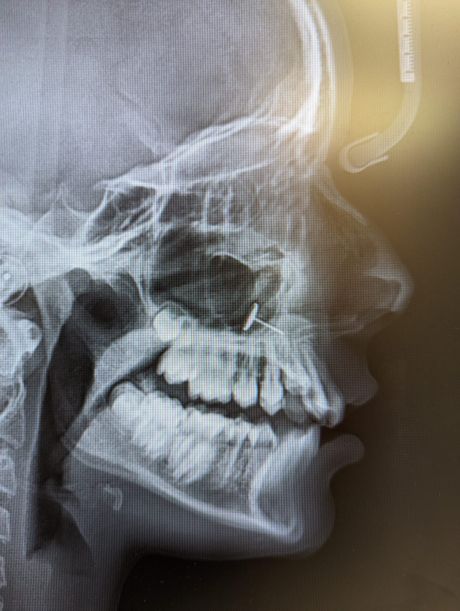

“Zubar se vratio sa rendgenskim snimkom i svi smo nekoliko minuta pokušavali da shvatimo šta gledamo”, rekla je majka.

Naime, na snimku se jasno video komad metala zaglavljen u sinusima tinejdžerke(!), ali majka nije umela da objasni kako je tamo dospeo. Istinu je znala devojčica, ali je ćutala.

Sve bi ostalo skriveno, da nije bilo pregleda kod zubara. Majka je objavila rendgenski snimak na Redditu koji je brzo postao viralan.